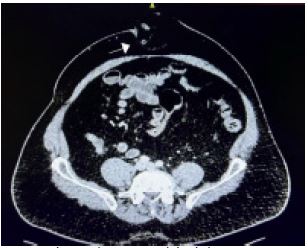

The CT report concluded: There is no free fluid in the abdomen and pelvis and no evidence of pneumoperitoneum. There is a substantial anterior abdominal wall midline hernia in the region of the umbilicus which contains non-compromised fat and the distal half of the appendix. The appendix does not appear particularly inflamed but the appendix within the hernial sac is dilated compared with the proximal appendix within the abdominal cavity which might imply a degree of obstruction at the level of the appendix entry into the hernial sac. (Figure 2) presents the CT imaging findings, demonstrating the presence of the appendix within the umbilical hernia.

Figure 2: Axial CT showing umbilical hernia containing the appendix as illustrated by the arrow.